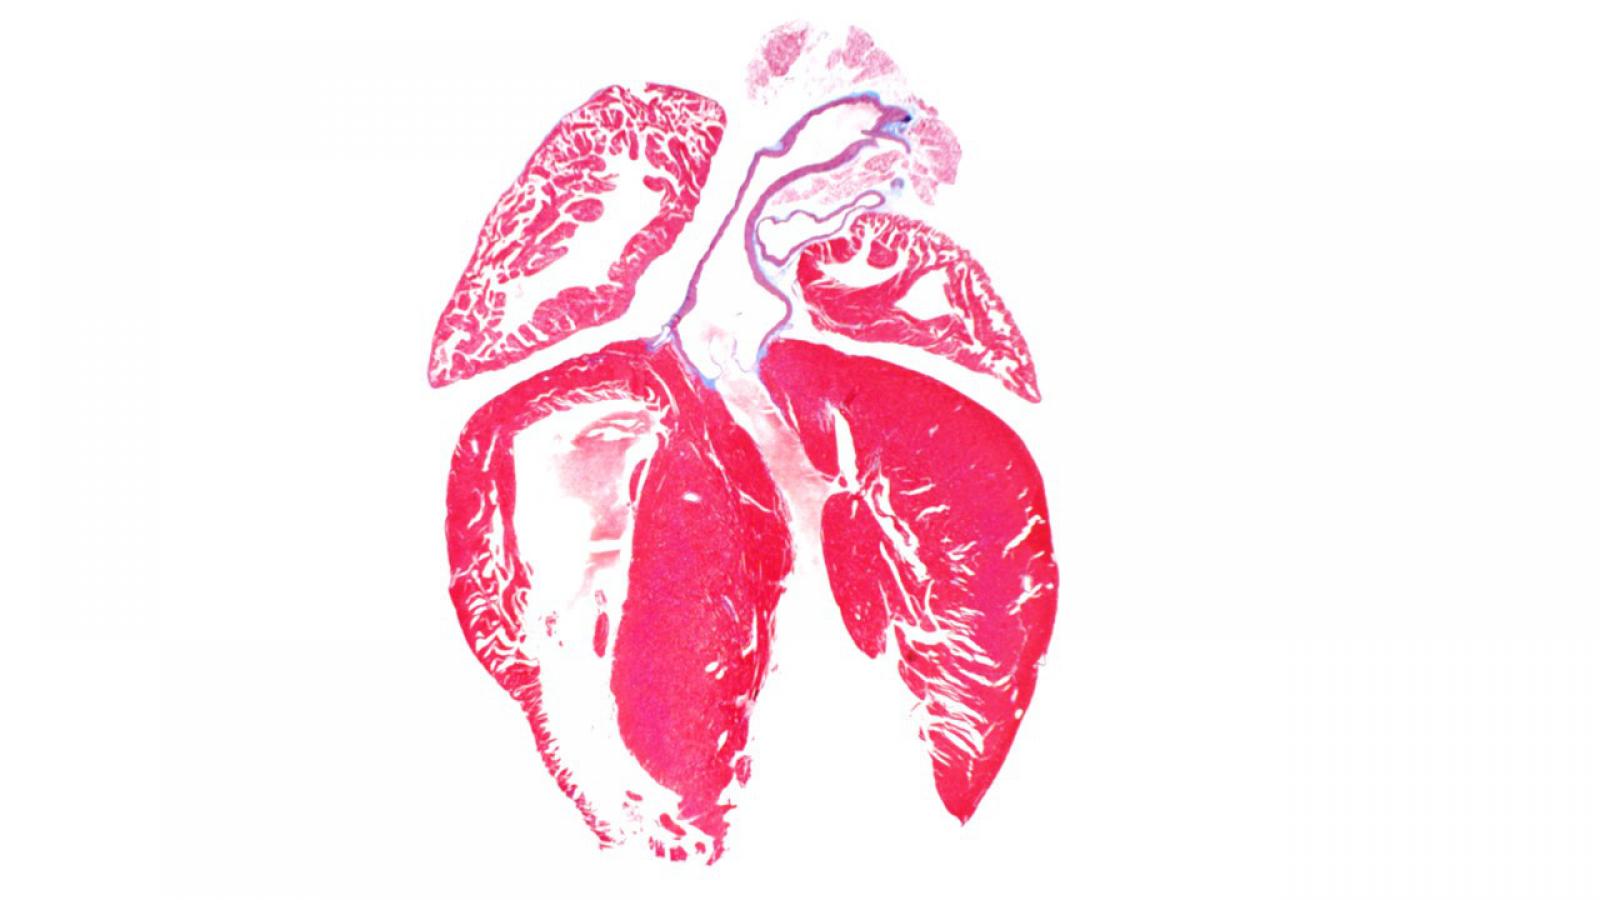

The Marx Lab studies the regulation of ion channels by macromolecular complexes. We have demonstrated that specific sequences within the ion channel (leucine zippers) recruit regulatory proteins, which modulate the ion channel function in normal and pathologic conditions. The laboratory is now focused on understanding the molecular components and functional implications of macromolecular complex formation of the large conductance calcium-activated potassium channel (BKCa, maxi-K) and the L-type voltage gated calcium channel. The laboratory utilizes both molecular biologic and electrophysiologic (planar lipid bilayer, patch clamp) techniques to elucidate these fundamental processes and emphasizes the links between these fundamental molecular processes and systems function. To date our work has had significant impact in understanding the triggers of fatal cardiac arrhythmias and mechanical dysfunction in heart failure. Present experiments are very likely to impact our understanding of control of peripheral blood pressure by the sympathetic nervous system.

The Marx Lab collaborates with the Wan Lab and the Morrow Lab to develop new methods of diagnosing and treating arrhythmias. Our scientists have made major advances in understanding the molecular and cellular bases for and the fundamental mechanisms of complex, life-threatening arrhythmias and sudden cardiac death. Our research program is focused in two major areas:

- Cardiac: studying the regulation of ion channels in normal and pathological conditions in the heart. Altered cardiac ion channel function is associated with heart failure and arrhythmias.

Our combined mission is to promote and stimulate interdisciplinary research in the cardiovascular field, with the overall goal of developing new and effective approaches for the diagnosis and treatment of diseases of the heart and blood vessels and the prevention of premature death.